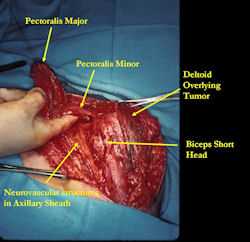

Examples of radical limb sparing surgeries for osteosarcomas in various anatomic locations (distal femur, proximal tibia, proximal humerus, scapula)

In each case, the tumor and bone from which it arose were resected. This required meticulous dissection, mobilization and preservation of adjacent pertinent neurovascular structures. In each case presented here, the defect was reconstructed with a special modular segmental tumor prosthesis. This also replaces the adjacent joint in many instances.

Proximal Humerus: Radical Limb Sparing Extra-Articular Resection and Prosethetic Reconstruction